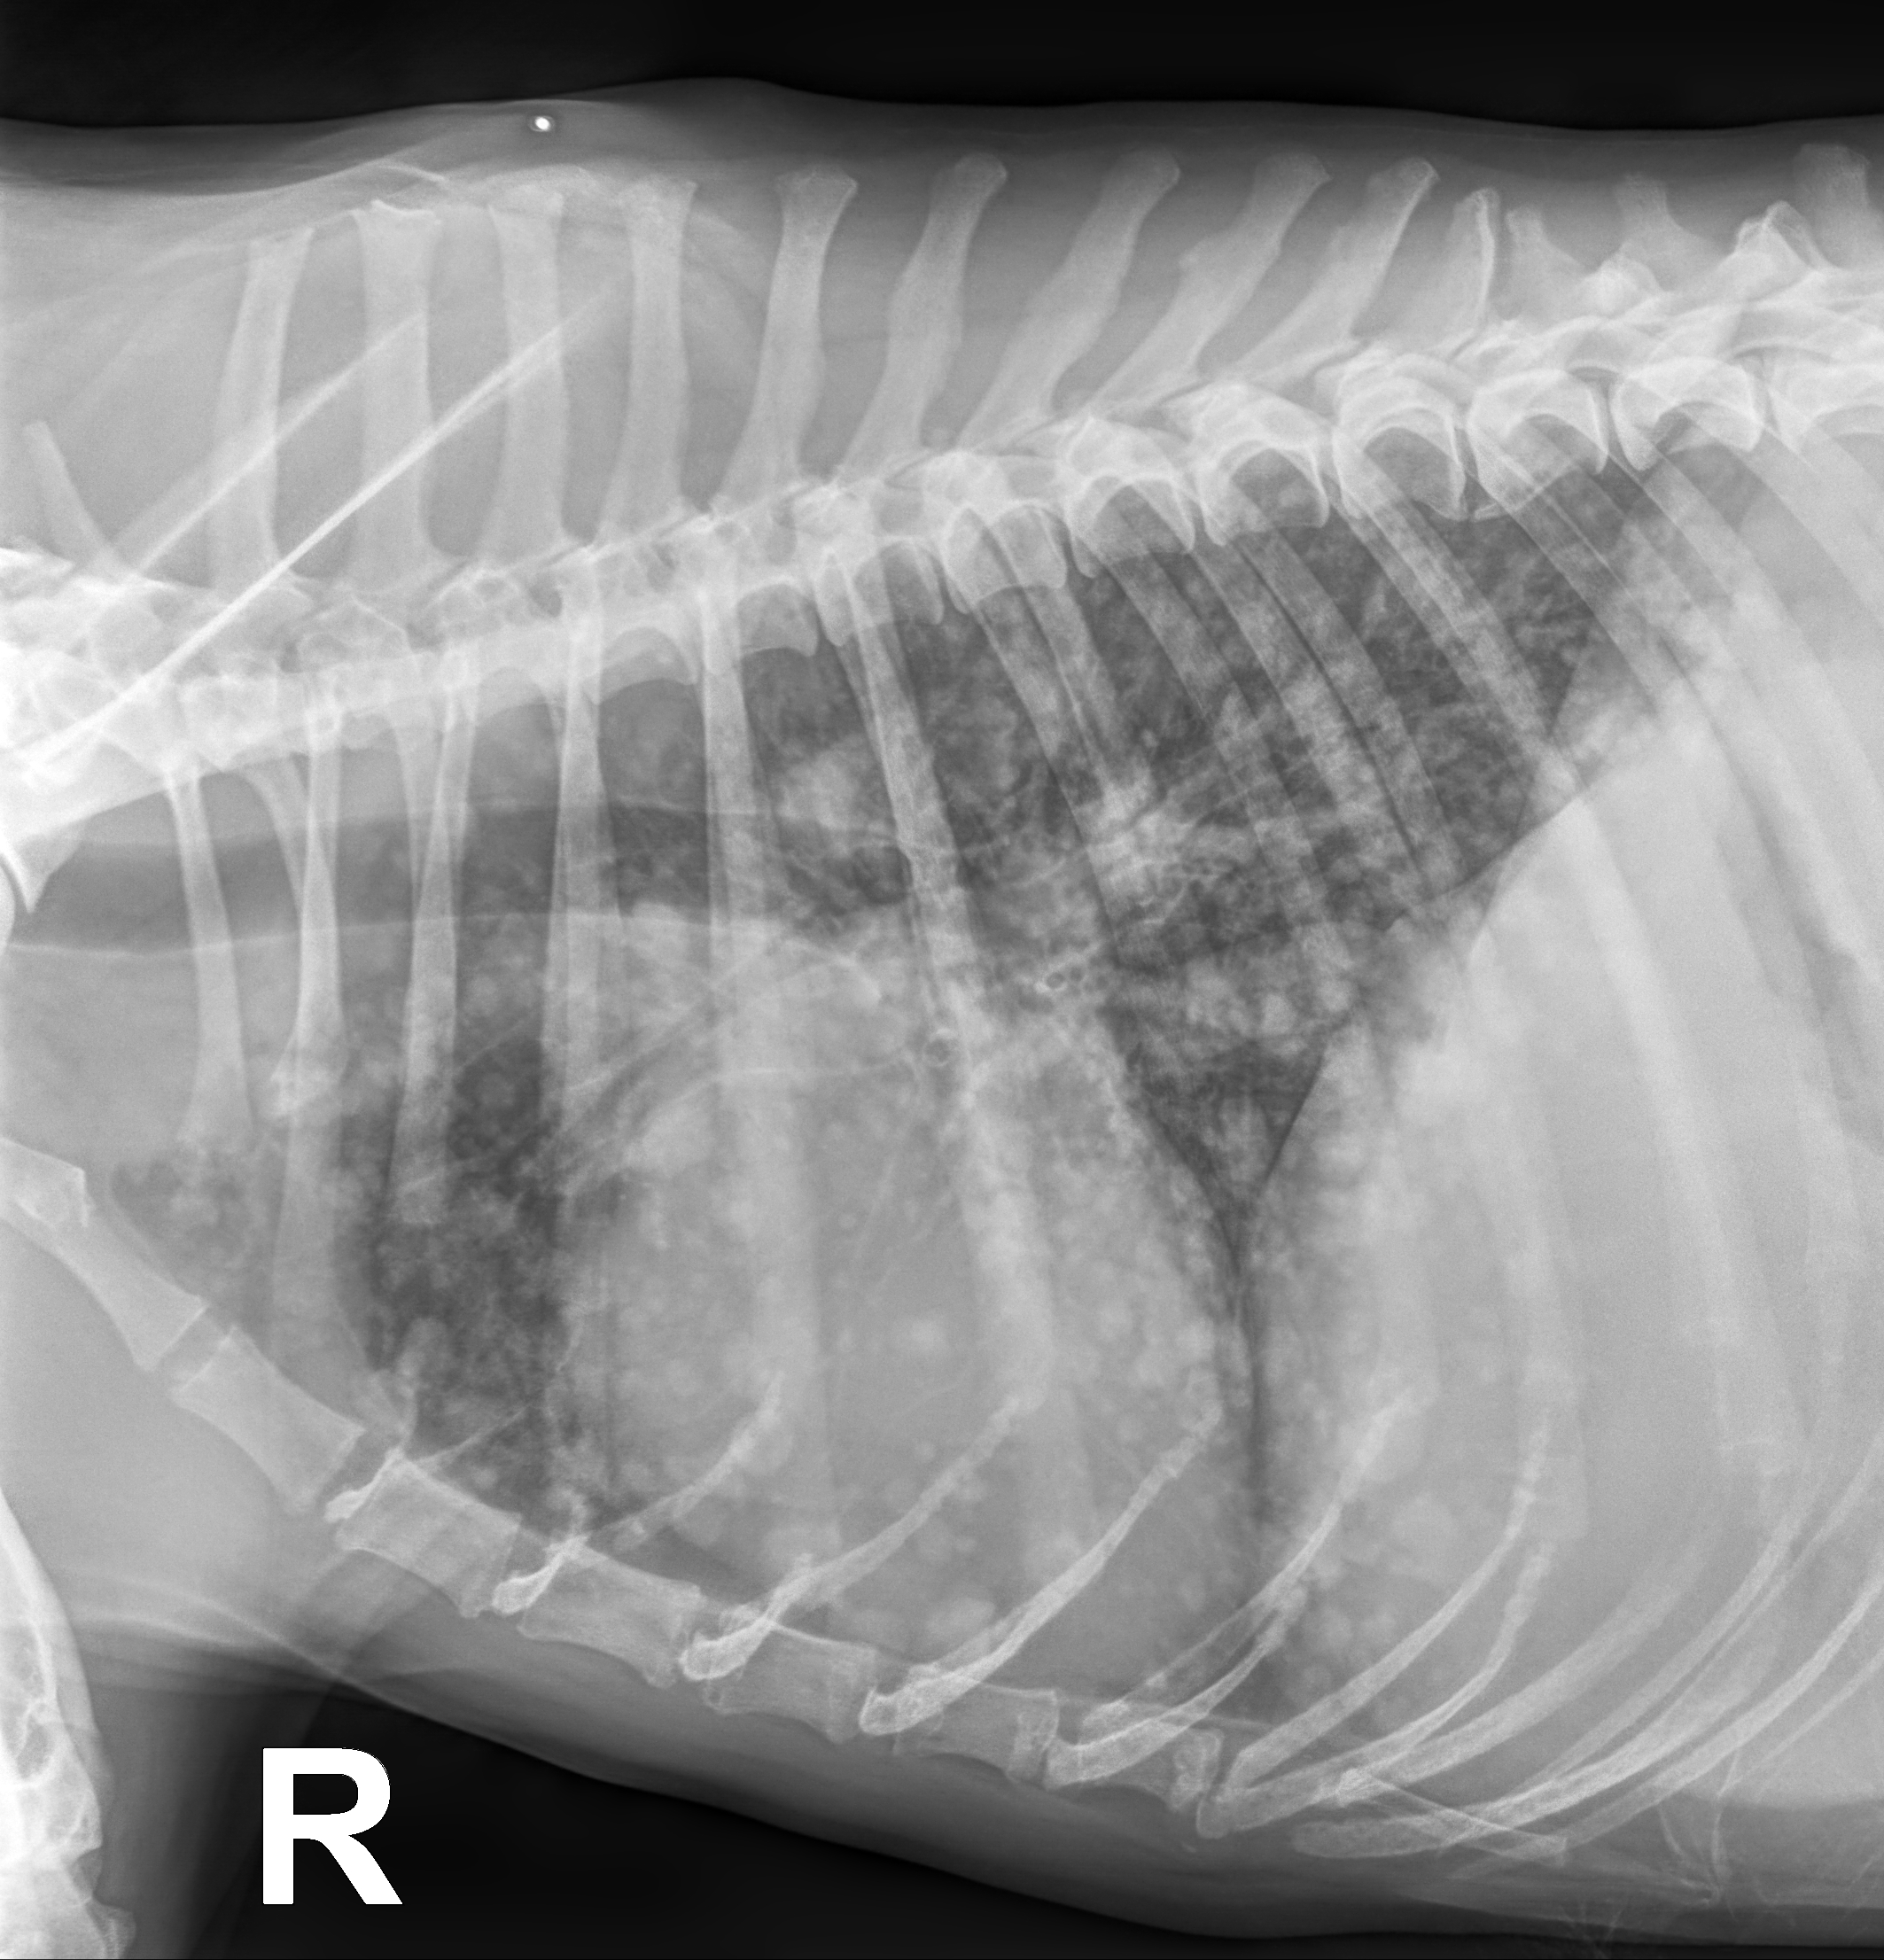

Am 10.- und 11.01.2026 ist alles Grau -in -Grau beim Röntgenkurs Thorax und Abdomen. Hier lernt garantiert jeder was dazu!